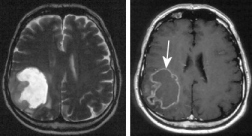

El

ácido desoxiribonucleico (ADN), esquema. El

DNS contiene grupos de nitrógeno que tienen

reacciones con el mercurio, y por eso la

substancia genética sufre un daño. La

"medicina convencional" no quiere

ver eso, y los gobiernos criminales y

calientes de la bolsa no bloquean el amalgama

hasta hoy... El ácido desoxiribonucleico (ADN), esquema. El DNS contiene grupos de nitrógeno que tienen reacciones con el mercurio, y por eso la substancia genética sufre un daño. La "medicina convencional" no quiere ver eso, y los gobiernos criminales y calientes de la bolsa no bloquean el amalgama hasta hoy...

Los elementos de la substancia genética (ADN = ácido desoxirribonucleico) contiene toda la información de la construcción del cuerpo y del metabolismo. Eso ADN contiene grupos de nitrógeno (N) que pueden reaccionar con el mercurio.

Las "letras" del ADN (incl. ADN mitocondrial) son cinco bases diversas. El mercurio se liga sobre todo al las bases timidina y uracilo, menos a adenosina, guanina o citosina. Por la formación de más radicales van ser provocados daños en la información genética, y eso puede provocar

-- cáncer

--  o la muerte celular.> (p.37)

El cerebro Alzheimer

perdió una grande parte de su substancia cuando

en comparación a un cerebro sano. El mercurio

esencialmente es una parte de ese proceso. El cerebro Alzheimer perdió una grande parte de su substancia cuando en comparación a un cerebro sano. El mercurio esencialmente es una parte de ese proceso.